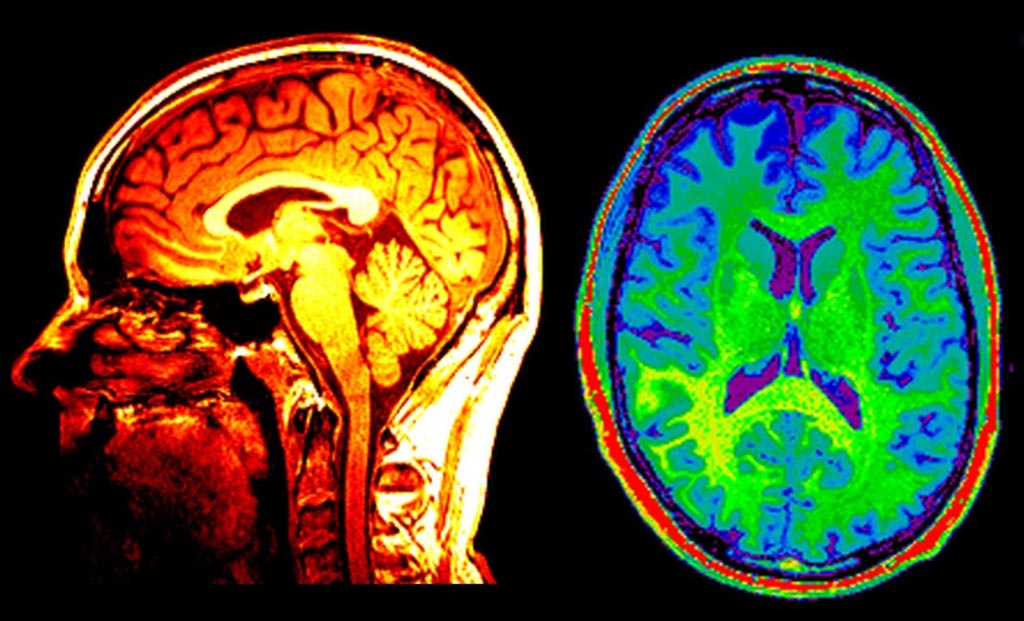

நான்காண்டுகளுக்கு முன்பு இதே போன்ற காந்த அதிர்வு படிமமாக்கச் சோதனை (Magnetic resonance imaging – MRI) ஒன்றை ஆண்ட்ரூ மேற்கொண்டிருந்தார். அப்போது அவரது மூளையில் எந்த சிக்கலும் இல்லை என்று மருத்துவர்கள் தெரிவித்திருந்தனர். எனினும், மீண்டும் அதே சோதனையை ஒரு முறை செய்து பார்த்து விட முடிவு செய்துள்ளார் அவரது மனைவி மோனா. அதன்படி ஆண்ட்ரூவின் மூளையை காந்த அதிர்வு படிமமாக்கச் சோதனைக்கு உட்படுத்தினர் மருத்துவர்கள். தற்போதைய பரிசோதனை முடிவுகளை ஆய்வு செய்த மருத்துவர்கள், மூளையில் கட்டிகளோ அல்லது இரத்தக்கசிவோ, அல்லது சிதைவுற்ற பகுதியோ இல்லை என்பதை உறுதி செய்ததோடு மூளை ஆரோக்கியமாக இருப்பதாகத் தெரிவித்துள்ளனர்.

இவ்விரு பரிசோதனை அறிக்கைகளையும் எடுத்துக் கொண்டு வாஷிங்டன் பல்கலைக்கழகத்தைச் சேர்ந்த நரம்பியல் வல்லுநர்களான மெரில் மற்றும் அவரது சகா சைரஸ் ராஜியை அணுகியுள்ளார் மோனா. ஆண்ட்ரூவின் பழைய மற்றும் புதிய பரிசோதனை முடிவுகளை நியூரோரீடர் எனும் மென்பொருளைக் கொண்டு ஒப்பிட்டுப் பார்த்த வல்லுநர்கள், அவர் அதிர்ச்சியின் விளைவாய் ஏற்படும் நாள்பட்ட மூளை பாதிப்பு நோய்க்கு (chronic traumatic encephalopathy – CTE) ஆளாகியுள்ளார் என்பதைக் கண்டுபிடித்தனர். இவ்வகையான மூளைபாதிப்பானது தலையில் ஏற்படும் தாக்குதல்களின் விளைவாய் மெல்ல மெல்ல மூளையின் திறன் பாதிப்புக்கு உள்ளாவதால் ஏற்படுகின்றது. பெரும்பாலும் அமெரிக்க கால்பாந்தாட்ட விளையாட்டு வீரர்கள் மற்றும் குத்துச்சண்டை வீரர்கள் இந்த நோய்க்கு ஆளாகின்றனர்.

ஆண்ட்ரூ நான்காண்டுகளுக்கு முன் எடுத்திருந்த எம்.ஆர்.ஐ சோதனையின் முடிவுகளையும் தற்போது எடுத்திருந்த அதே சோதனையின் முடிவுகளையும் மிக நுணுக்கமாக ஆராய்ந்தது நியூரோரீடர். பொதுவாக எம்.ஆர்.ஐ சோதனை அறிக்கையை மருத்துவர்கள் பரிசோதிப்பர்; பின், அதில் ஏதும் மாறுபாடுகள் தட்டுப்பட்டால் அது தொடர்பான சிகிச்சையை பரிந்துரை செய்வர்.

நியூரோரீடர் மென்பொருள் ஒருவரிடம் வெவ்வேறு சந்தர்பங்களில் எடுக்கப்பட்ட எம்.ஆர்.ஐ சோதனையின் முடிவுகளை ஒப்பிட்டுப் பார்க்கிறது. பழைய மற்றும் புதிய முடிவுகளில் வெளிப்படும் மிக நுணுக்கமான மாறுபாடுகளை கண்டறிந்து மருத்துவரிடம் சொல்லி விடுகிறது. அதன் பின் அறிவாற்றல் சோதனைகள் (Cognitive Tests) உள்ளிட்ட வழமையான சோதனைகளை மேற்கொள்ளும் மருத்துவர்களால் ஓரளவுக்குத் துல்லியமாக மூளையில் ஏற்பட்டுள்ள பாதிப்பின் தன்மையை கண்டறிந்து அதற்கேற்ப சிகிச்சை முறையைத் தீர்மானிக்க முடிகிறது.